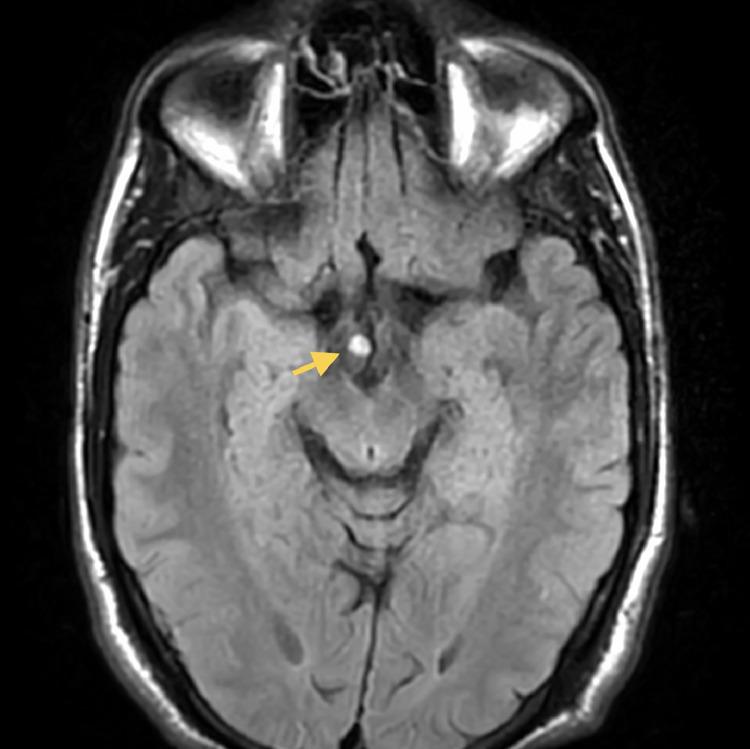

A 45-year-old male patient with clinically suspected schizophrenia was referred for an MRI brain to look for organicity. An incidental lesion was noted on the right side of the tubercinerium with suspicious findings of osteolipoma. T1 and T2 weighted sequences showed a hyper-intense lesion suggestive of fatty intensity or hemorrhage. A homogenous blooming artefact was seen on gradient imaging suggestive of a calcific/hemorrhagic element. The referring clinician was conveyed the findings asking about the need for further imaging by CT. The patient was started on antipsychotics for schizophrenia. One week later, a CT head was obtained, which showed a fatty density lesion with a smooth, peripheral rim of hyperdensity. The HU value matched rim calcification suggesting radiological diagnosis of osteolipoma. The patient was kept under close observation and no specific therapy was guided to this lesion. The patient was responding well to pharmacotherapy (in terms of control of symptoms) confirming osteolipoma as an incidental finding. This case report establishes the role of adequate imaging in subtle brain lesions which may mimic primary lesion-producing neurological symptoms. The importance of clinical judgment and follow-up in guiding suitable therapy is also highlighted.

一名45岁男性患者,临床怀疑患有精神分裂症,因排查器质性病变接受脑部MRI检查。在松果体右侧发现一个意外病变,怀疑为骨脂瘤。T1加权序列和T2加权序列显示一个高强度病变,提示为脂肪密度或出血。梯度成像上可见均匀的磁敏感伪影,提示存在钙化/出血成分。已将检查结果告知转诊的临床医生,并询问是否需要进一步进行CT成像检查。该患者开始使用抗精神病药物治疗精神分裂症。一周后,进行了头颅CT检查,结果显示一个脂肪密度病变,周边有光滑的高密度边缘。HU值与边缘钙化相符,提示骨脂瘤的影像学诊断。该患者接受密切观察,未针对此病变进行特殊治疗。患者对药物治疗反应良好(症状得到控制),证实骨脂瘤为偶然发现。本病例报告确立了充分成像在可能模拟原发性病变所致神经症状的细微脑部病变中的作用。同时也强调了临床判断和随访在指导合适治疗方面的重要性。